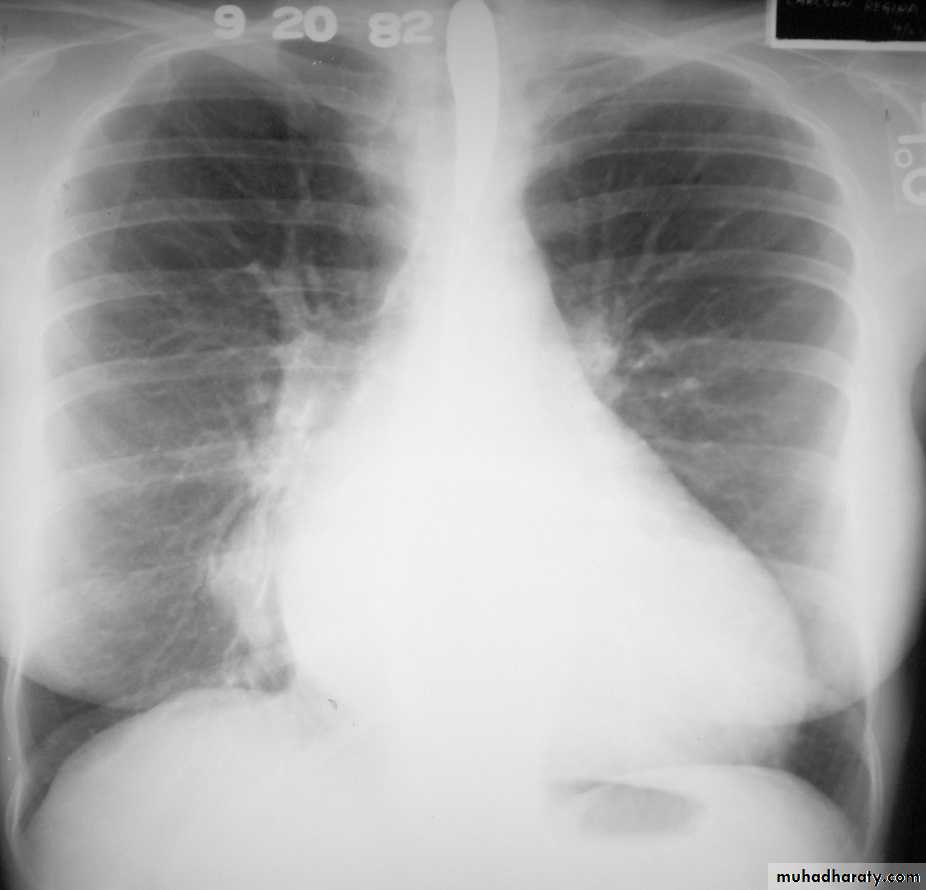

Pulmonary arterial hypertension results from elevation of the resistance in the pulmonary arterial bed, usually at the arteriolar level. It is characterized radiographically by enlargement of the pulmonary trunk and right and left main pulmonary arteries with disproportionately small peripheral vessels This has been referred to as "pruning" of the pulmonary arteries

So the Plain radiograph

elevated cardiac apex due to right ventricular hypertrophy

enlarged right atrium

prominent pulmonary outflow tract

enlarged pulmonary arteries

pruning of peripheral pulmonary vessels